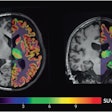

Trained using 414 patients clinically diagnosed with Alzheimer's disease and normal controls in the ADNI, the researchers' fully convolutional neural network (CNN) generates color-coded disease probability maps after analyzing T1-weighted brain MR images. Next, a multilayer perceptron analyzes these disease probability maps to produce a binary classification of Alzheimer's disease status.

"Not only can we accurately predict the risk of Alzheimer's disease but this algorithm can generate interpretable and intuitive visualizations of individual Alzheimer's disease risk en route to accurate diagnosis," Kolachalama said in a statement.